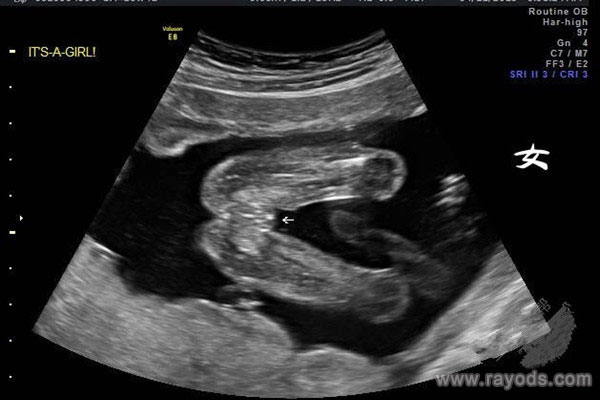

躺下之后医生说我肚子还不明显,但胎儿发育很好,还挺活泼,个人觉得这外面的要比医院的仔细和心细的多,大医院人多的原因吧也许是。然后这个医生看了很久胎儿的那个部位,都说看不大清楚,黑乎乎的,说女孩的几率很大,当时我也就没多想,觉得就是个女孩。

在网上查了一些资料,都说如果5个半月时已经清晰明显看到胎儿宝宝的生殖器的话,那胎儿性别就八九不离十了。如果已经真实看到胎儿宝宝是女孩,有女孩的性别特征,那就是女孩,如果看不清楚或者其他因素导致无法准确判断的情况时,可再次检查,这种模糊情况下是不能直接下定论的。

网上不少已生宝妈都表示,在5个半月的时候从胎儿屁股下面照上去,男孩的生殖器非常明显很好判断,有的说一个圆球上有个小尖尖,就像是一个茶壶一样,有的则说像个小乌龟,总而言之就是男孩的甚至会明显下来,往外凸。

而女孩的生殖器也有一个鼓包,但是没有小尖尖,凸出也不明显,仔细看的话会看到白线,这就是女孩的大小***。

对于这个结论,不少做了b超看男女性别的宝妈都说很准,男孩女孩的性别器官很好判断。所以说,如果是没看清楚或者是因为体位的原因看不清楚的大家不要着急着下结论,很有可能误判,就出现了男孩看成女孩,最后生了男孩的情况,把女孩看成男孩,最后生了女孩的情况。其实并不是所谓的女翻男,这只是当时误判的结果。